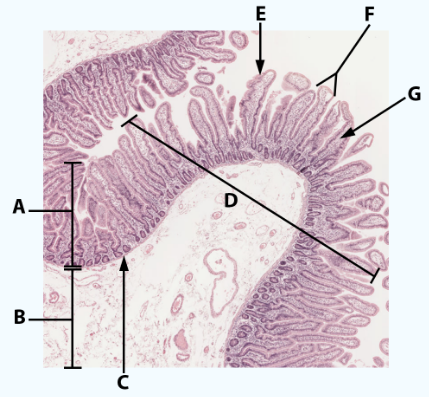

A

Mucosa: simple columnar epithelium with microvilli

B

Submucosa

C

muscularis mucosa

Area

Small intestine

E

simple columnar epithelium with goblet cells and microvilli

F

Villi

G

Lamina propria